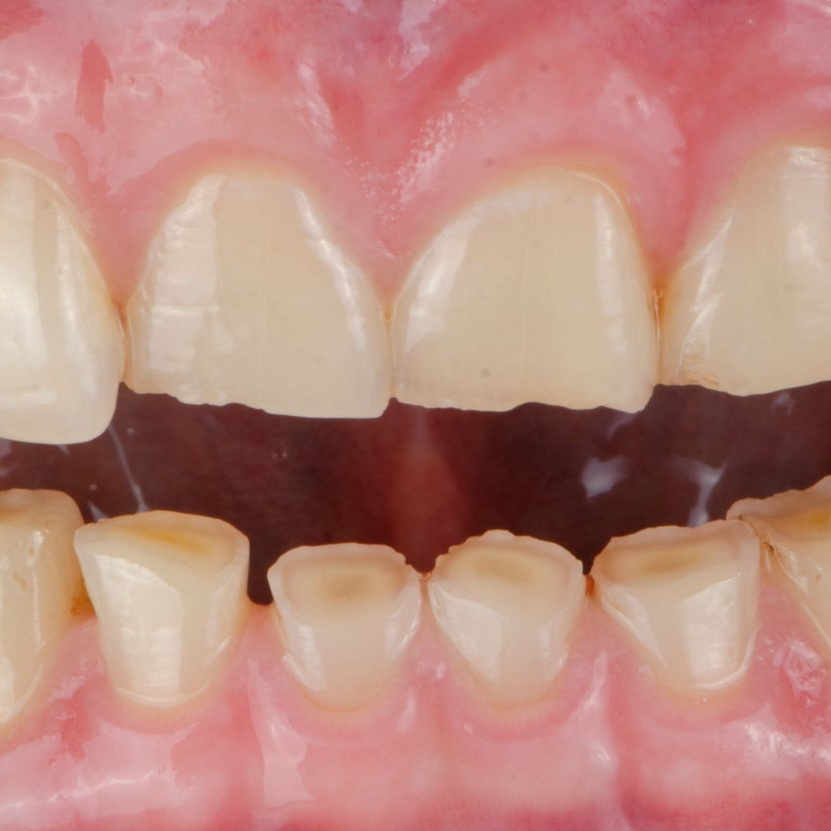

Durch das ständige Knirschen entstehen Abrasionen (= Abrieb) auf den Zähnen, wodurch diese kürzer werden und auch ihre Form verändern. Dies kann soweit führen, dass der Schmelz an einzelnen Stellen vollständig weggeknirscht wird und das darunterliegende gelbliche Dentin zum Vorschein kommt. Da das Dentin von mikroskopisch kleinen Kanälchen durchzogen ist, in denen Ausläufer von Nervenzellen liegen, kann dies beim Kauen zu Empfindlichkeiten führen. Außerdem ist das Dentin deutlich weicher als der Zahnschmelz, so dass sich der Abrieb an diesen Stellen beschleunigt

Durch das ständige Knirschen entstehen Abrasionen (= Abrieb) auf den Zähnen, wodurch diese kürzer werden und auch ihre Form verändern. Dies kann soweit führen, dass der Schmelz an einzelnen Stellen vollständig weggeknirscht wird und das darunterliegende gelbliche Dentin zum Vorschein kommt. Da das Dentin von mikroskopisch kleinen Kanälchen durchzogen ist, in denen Ausläufer von Nervenzellen liegen, kann dies beim Kauen zu Empfindlichkeiten führen. Außerdem ist das Dentin deutlich weicher als der Zahnschmelz, so dass sich der Abrieb an diesen Stellen beschleunigt.